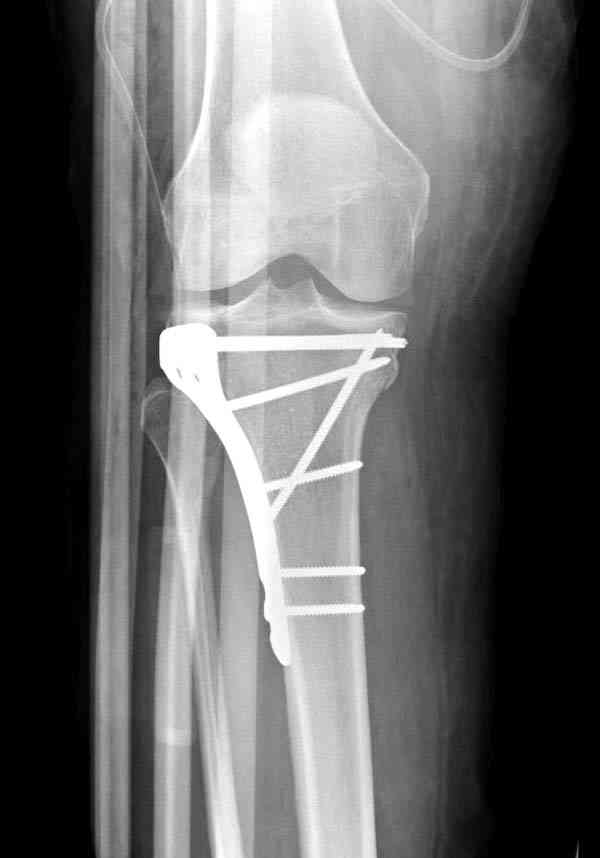

Нет, малоберцовый внизу, фиксацию проводим на верхнем эпифизе, где твердая кость. Задача состоит

в том, чтобы создать арматуру из нескольких проведенных шурупов на эпифизе.

Медиально, обычно на протовоположной

строне, делается окно в кортикальном слое, кривым забойником под рентгеном поднимается импрессия.

После заполнения образовавшейся полости в метафизе

кортикальное окно можно прикрыть.

Это техника применяется, когда имеется

центральная импрессия, а при ипрессии с краевым переломом - после приподнимания импрессии опорная (Butress) пластина, как на снимке.